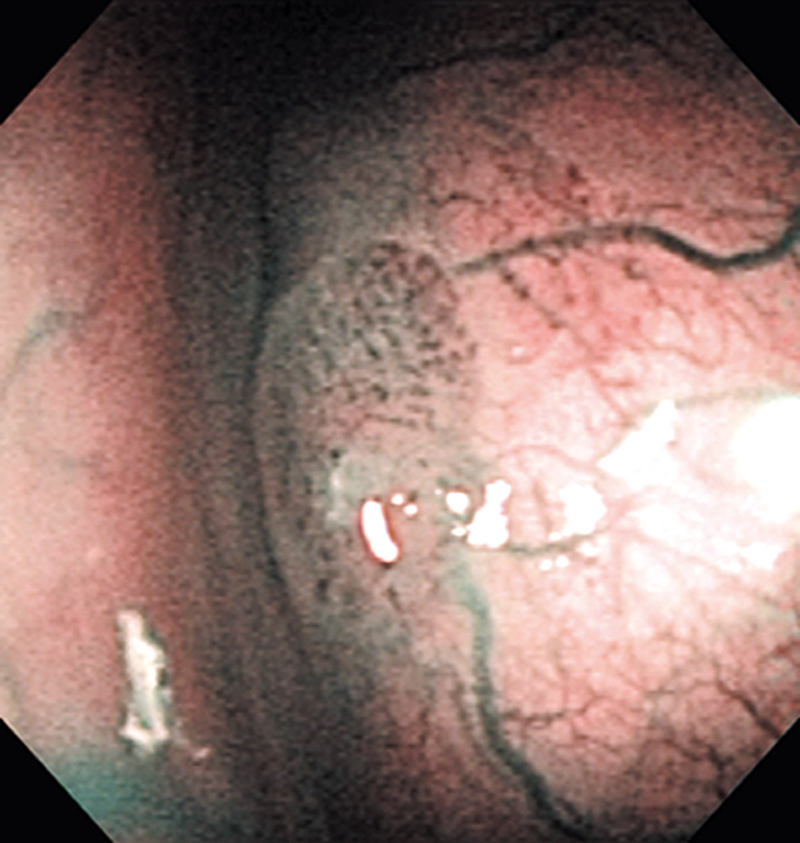

Hypopharynx Cancer (Right Pyriform Sinus) Aged 57, male

NBI

The lesion was detected on the right pyriform sinus in a head/neck cancer screening with NBI laryngopharyngoscopy before an esophageal carcinoma surgery.

The NBI image showed an irregular shaped brownish lesion. In the conventional white light image, a slight reddening was observed but the boundary was hard to identify.

The lesion was 9 x 6 mm, treated with endoscopic mucosal resection and diagnosed as a carcinoma in situ.